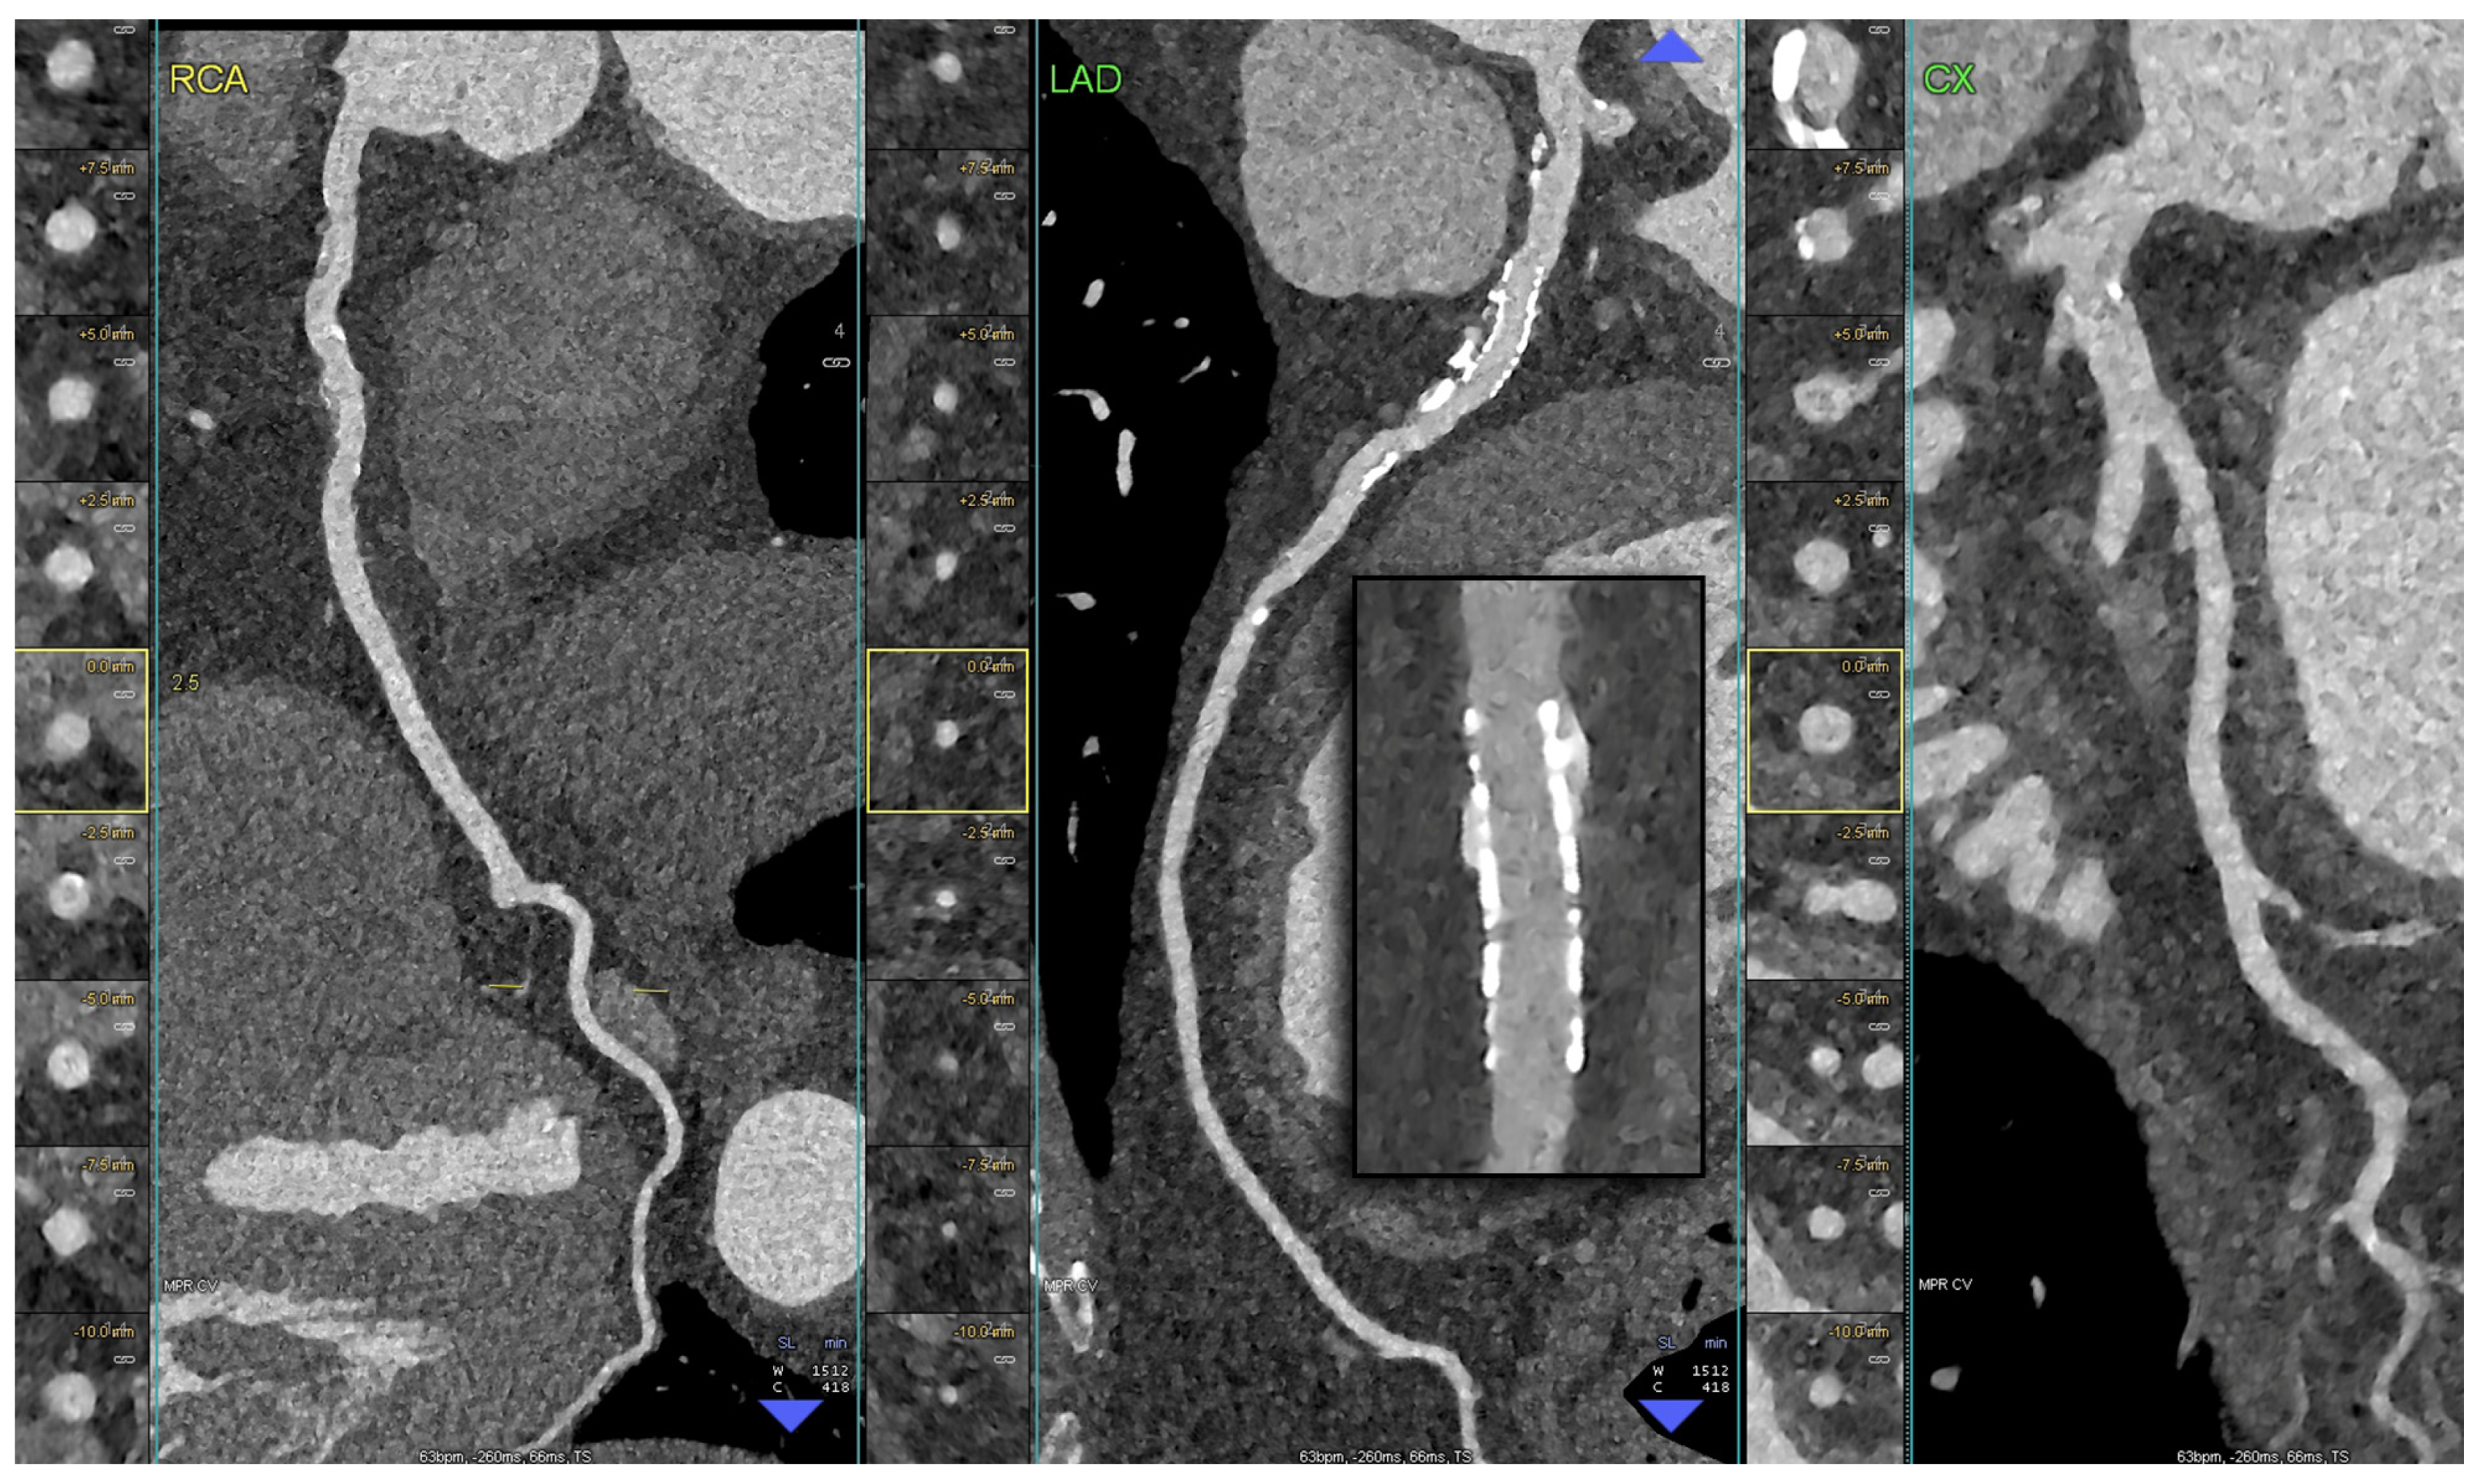

5. Clinical Application of PCCT in Coronary Plaque

- Si-Mohamed, S.A.; Boccalini, S.; Lacombe, H.; Diaw, A.; Varasteh, M.; Rodesch, P.-A.; Dessouky, R.; Villien, M.; Tatard-Leitman, V.; Bochaton, T.; et al. Coronary CT Angiography with Photon-counting CT: First-In-Human Results. Radiology 2022, 303, 303–313. [Google Scholar] [CrossRef]

- Mergen, V.; Eberhard, M.; Manka, R.; Euler, A.; Alkadhi, H. First in-human quantitative plaque characterization with ultra-high resolution coronary photon-counting CT angiography. Front. Cardiovasc. Med. 2022, 9, 981012. [Google Scholar] [CrossRef]

- Rotzinger, D.C.; Racine, D.; Becce, F.; Lahoud, E.; Erhard, K. Performance of spectral photon-counting coronary CT angiography and comparison with energy-integrating-detector CT: Objective assessment with Performance of Spectral Photon-Counting Coronary CT Angiography and Comparison with Energy-Integrating-Detector. Diagnostics 2021, 11, 2376. [Google Scholar] [CrossRef] [PubMed]

- Boussel, L.; Coulon, P.; Thran, A.; Roessl, E.; Martens, G.; Sigovan, M.; Douek, P. Photon counting spectral CT component analysis of coronary artery atherosclerotic plaque samples. Br. J. Radiol. 2014, 87, 20130798. [Google Scholar] [CrossRef]

- Baturin, P.; Alivov, Y.; Molloi, S. Spectral CT imaging of vulnerable plaque with two independent biomarkers. Phys. Med. Biol. 2012, 57, 4117–4138. [Google Scholar] [CrossRef]

- Vanmeter, P.; Marsh, J.; Rajendran, K.; Leng, S.; Mccollough, C. Quantification of Coronary Calcification using High-Resolution Photon-Counting-Detector CT and an Image Domain Denoising Algorithm. In Medical Imaging 2022: Physics of Medical Imaging; SPIE: Bellingham, DC, USA, 2022; pp. 1–10. [Google Scholar] [CrossRef]

- Vattay, B.; Szilveszter, B.; Boussoussou, M.; Vecsey-Nagy, M.; Lin, A.; Konkoly, G.; Kubovje, A.; Schwarz, F.; Merkely, B.; Maurovich-Horvat, P.; et al. Impact of virtual monoenergetic levels on coronary plaque volume components using photon-counting computed tomography. Eur. Radiol. 2023, 33, 8528–8539. [Google Scholar] [CrossRef] [PubMed]